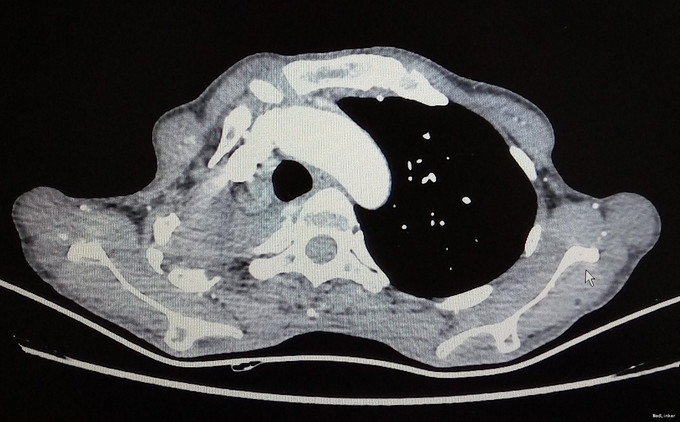

查体:生命体征平稳,腹部饱满,无腹壁静脉曲张,腹韧,无压痛、反跳痛及肌卫,移动性浊音(+),肠鸣音6次/分。 辅助检查:胸部CT:右肺缺如。血钾:3.24mmol/l(见图1-2)。